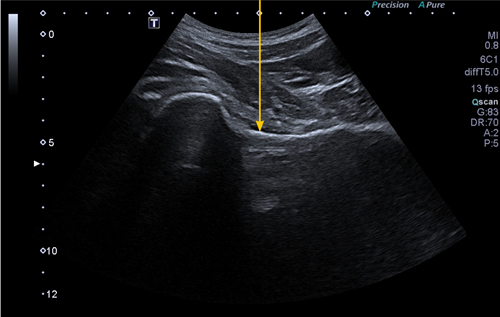

Figura 1

Material y método: Estudio observacional retrospectivo sobre cohorte de pacientes con coxartrosis sintomática, tratados mediante viscosuplementación intrarticular ecoguiada de cadera con dos tipos de inyección única de ácido hialurónico. Su eficacia fue evaluada de acuerdo con las escalas WOMAC y EVA a los 6 y 12 meses.